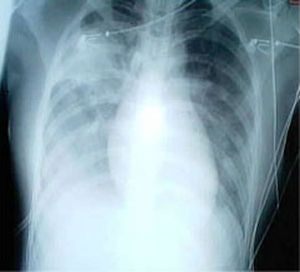

흉부 방사선 사진은 폐렴 진단에 흔히 사용된다.[141] 경증 환자는 잠재적 합병증이 있거나, 치료에 호전되지 않거나, 원인이 불확실한 경우에만 영상 검사가 필요하다.[141][65] 입원이 필요할 정도로 중증인 경우 흉부 방사선 사진이 권장된다.[65] 방사선 소견이 항상 질병의 중증도와 일치하지는 않으며, 세균성과 바이러스성 감염을 확실하게 구분하지 못한다.[141]

폐렴의 X선 사진 소견은 섬엽 폐렴, 세기관지 폐렴, 소엽 폐렴, 간질성 폐렴으로 분류할 수 있다.[66] 세균성, 급성 폐렴은 고전적으로 폐 분절엽 하나의 폐 실질 침윤을 보이는데, 이를 섬엽 폐렴이라고 한다.[72] 그러나 소견은 다양할 수 있으며, 다른 유형의 폐렴에서는 다른 양상이 흔하다.[72] 흡인성 폐렴은 주로 폐 아래쪽과 오른쪽에 양측성 음영으로 나타날 수 있다.[72] 바이러스성 폐렴의 X선 사진은 정상, 과팽창, 양측성 반점, 또는 섬엽 폐렴과 유사한 폐 실질 침윤으로 나타날 수 있다.[72] 특히 탈수가 있는 경우 질병 초기에는 방사선학적 소견이 없거나, 비만 또는 폐 질환 병력이 있는 사람은 해석하기 어려울 수 있다.[140] 흉막 삼출과 같은 합병증도 흉부 방사선 사진에서 발견될 수 있다. 측면 흉부 방사선 사진은 폐 실질 침윤과 흉막 삼출 진단 정확도를 높일 수 있다.[78]